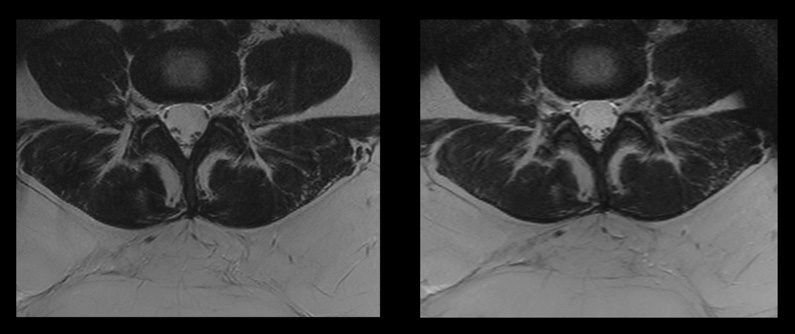

Compressed SENSE reduziert die SAR zum Vorteil des Patienten. Dies macht auch die Entscheidung leichter, Patienten mit herausfordernden Fragestellungen anzunehmen.

Patienten mit Metallimplantaten und anderen besonderen Voraussetzungen können in der MRT wegen der spezifisch erforderlichen SAR-Werten eine Herausforderung darstellen. Wenn Sie Compressed SENSE in Ihre ExamCard integrieren, können Sie die gesamte MR-Untersuchungsdauer reduzieren, sodass die SAR innerhalb der vom Hersteller des bedingt MR-sicheren Implantats angegebenen Grenzen bleibt. So können auch Patienten gescannt werden, für die eine MR-Untersuchung andernfalls abgelehnt werden müsste. Die kürzere Scandauer kommt gleichzeitig auch dem Patientenkomfort zugute.

Links: Herkömmlicher Scan mit SAR von 2,5 W/kg und Scandauer 7:33 Minuten

Rechts: Compressed SENSE Scan mit SAR 1,9 W/kg und Scandauer 3:21 Minuten